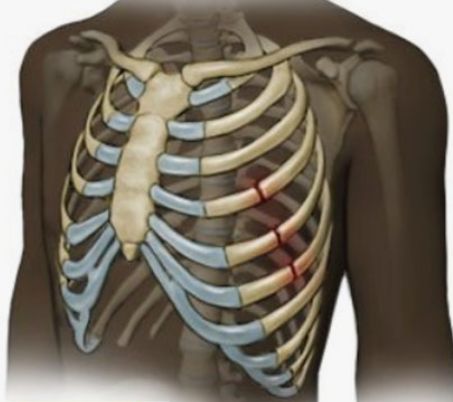

이 사고로 A씨는 좌측 늑골(갈비뼈) 골절과 우측 정강이 열상 등의 부상을 입었으며, 추석 연휴 기간 통원치료를 받은 뒤 지난달 20일 업무에 복귀한 것으로 알려졌다.